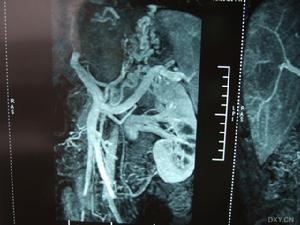

《布-加綜合徵的診斷與治療》2.ct、mra具有較高的診斷價值。